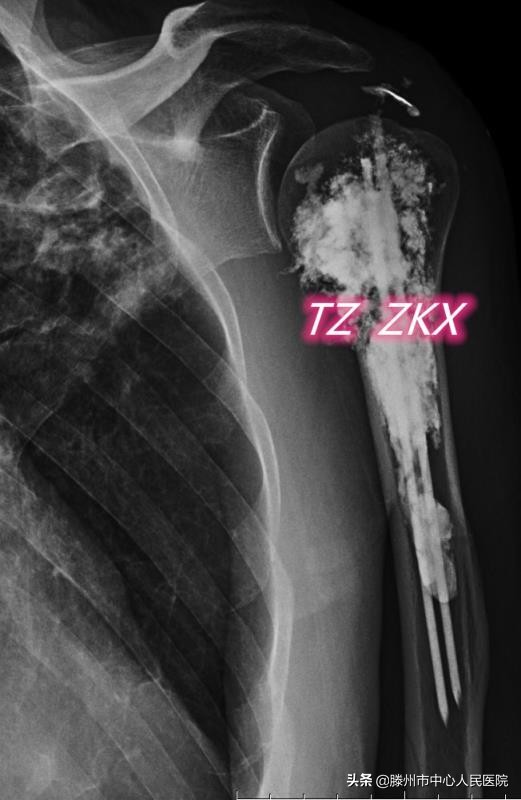

8月11日,張開賢主任醫(yī)師團(tuán)隊(duì)在麻醉科的協(xié)助下,采用臂叢麻醉,在CT引導(dǎo)下經(jīng)皮穿刺,首先對病變區(qū)域進(jìn)行微波消融,利用高溫使腫瘤發(fā)生凝固性壞死,然后在肱骨髓腔內(nèi)置入兩根克氏針,最后注射骨水泥,使克氏針、骨水泥與肱骨融合在一起,從而起到殺滅腫瘤、緩解疼痛、增加骨骼的穩(wěn)定性、預(yù)防病理性骨折的作用。

微波消融聯(lián)合鋼筋混凝土技術(shù)治療骨轉(zhuǎn)移為國內(nèi)領(lǐng)先的微創(chuàng)治療技術(shù),優(yōu)勢在于:在臂叢麻醉下進(jìn)行,減少了全身麻醉對身體的不良影響;經(jīng)皮穿刺完成整個治療流程,創(chuàng)傷小,術(shù)后恢復(fù)快,住院時間短;在CT引導(dǎo)下進(jìn)行,能精準(zhǔn)地觀察克氏針的空間位置、骨水泥的分布及滲漏情況,保證了治療的安全性,同時與DSA下操作相比,減少了射線對醫(yī)務(wù)人員的輻射。